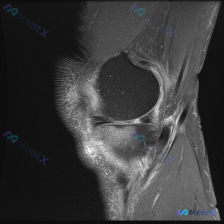

病例读片分享:临床怀疑半月板异常,MRI却只看到髌周病变 基本影像信息 提供的影像为膝盖MRI-T2序列矢状位,切面位于膝关节前部髌股关节区域,图像存在一定截断伪影,未显示后交叉韧带及大部分后侧软组织结构。 影像核心发现 整理一下客观观察到的异常: 1. 髌前皮下软组织水肿:髌骨前方及皮下组织层可见...

看到这份有意思的病例,主诉是提示半月板异常的膝关节MRI,整理了完整的读片思路和分析,分享给大家。 一、影像基础信息 这是一幅膝关节MRI T2加权矢状位图像,我们先确认基础信息: - 成像序列符合T2WI特征:液体高信号、软骨中等信号、脂肪低信号、骨皮质及韧带低信号 - 切面展示膝关节前部结构:髌...